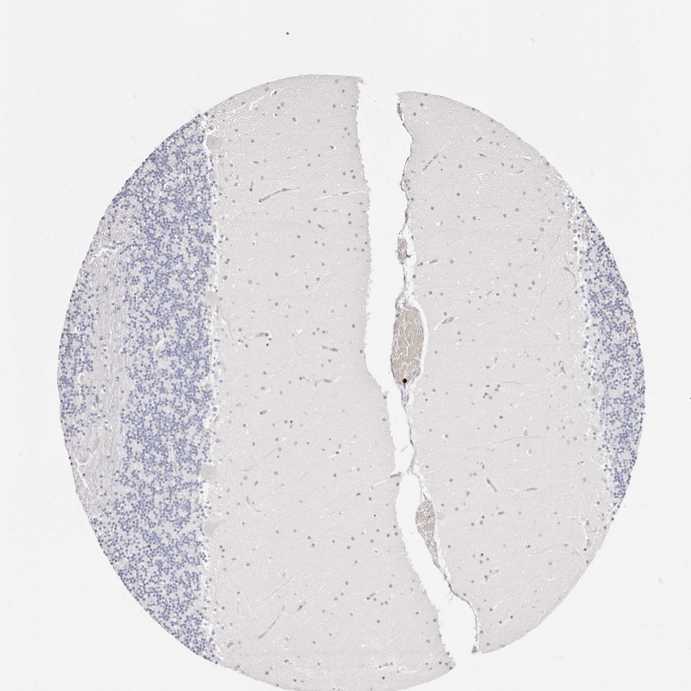

CEREBELLUM - Antibody stainingi

Antibody staining in the annotated cell types in the current human tissue is reported as not detected, low, medium, or high, based on conventional immunohistochemistry profiling in selected tissues. This score is based on the combination of the staining intensity and fraction of stained cells.

Each image is clickable and will lead to virtual microscopy that enables deeper exploration of all samples and also displays staining intensity scores, fraction scores and subcellular localization as well as patient and tissue information for each sample.

Antibody HPA029874Antibody CAB015949Antibody CAB016522

Purkinje cells Not detectedNot detectedMedium

Cells in granular layer Not detectedNot detectedNot detected

Cells in molecular layer Not detectedNot detectedNot detected